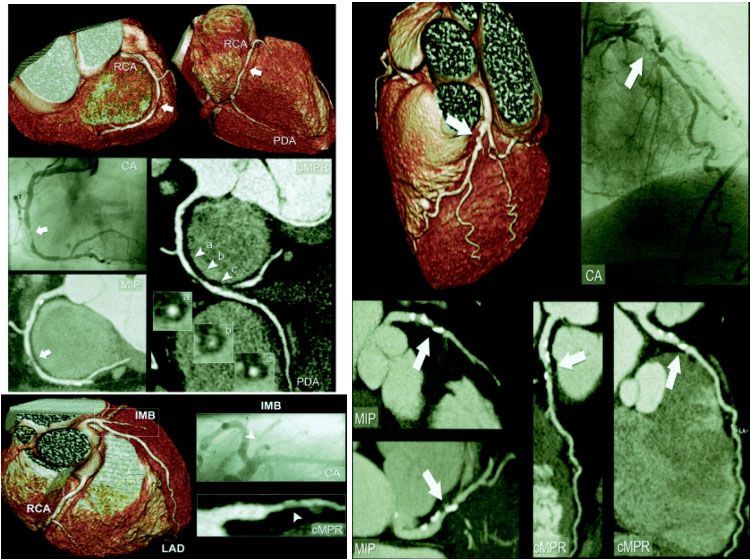

![]() |

| Рис.5. КАГ (E, F) и МСКТ коронарных артерий( A, B, C, D). Гемодинамически значимый стеноз ПКА (стрелки). |